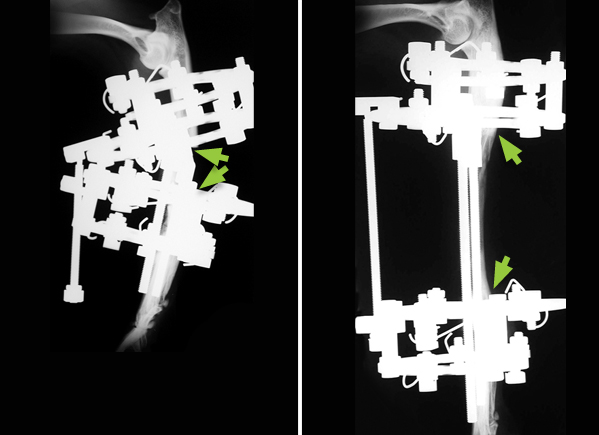

Case 1

A Boxer pup with a shortened, deformed right forelimb due to one the forearm bones (the radius) not forming during development, a condition known as radial agenesis (arrow shows where the radius should be). Only the ulnar bone is present. As a result the forearm is short and the paw has collapsed inwardly due to a lack of support.

In the first operation the paw was straightened and fused to the ulnar bone. In the second operation the ulnar bone was lengthened (compare the distance between the arrows in the two X-rays) using pins, rings and threaded connecting bars.

X-ray and photograph of the same Boxer as an adult dog, showing the straightened and lengthened limb. There is no movement in the carpus (wrist joint) because it has been fused.